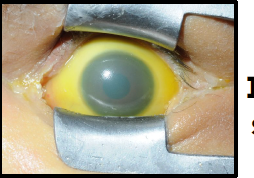

icteric sclera

iris coloboma